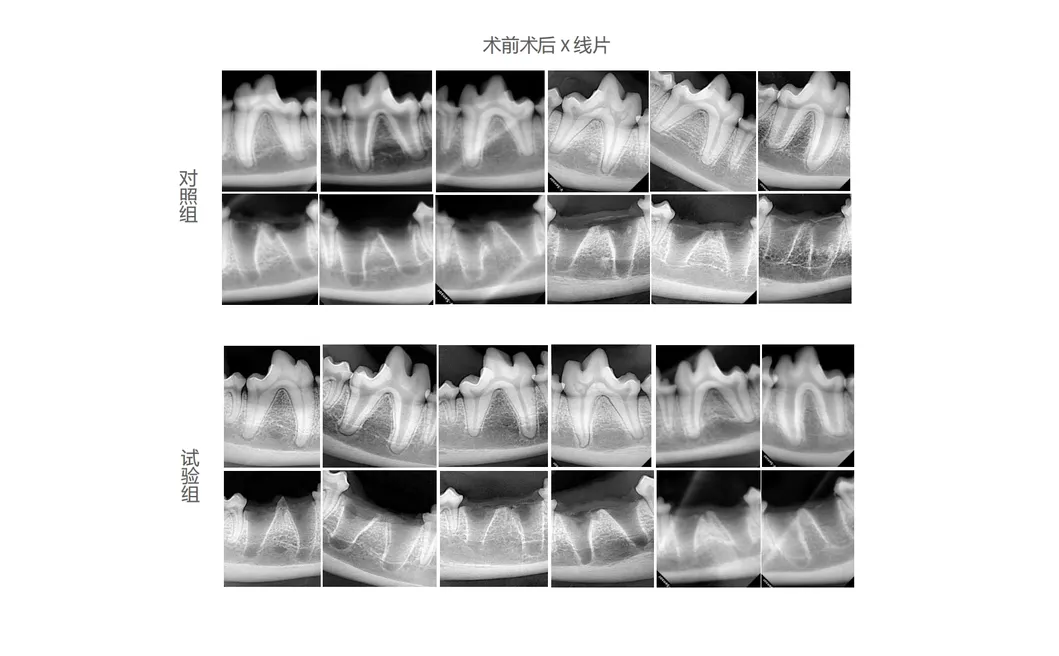

Dogs were meticulously chosen as the prime experimental subjects to evaluate the effectiveness of new-age dental instruments. The control group used conventional manual tools, while the treatment group used the state-of-the-art Pneumatic Dental Elevator Kit. Researchers monitored physiological parameters, complication incidence, extraction time, and site trauma. Data indicated profound insights into the performance advantages of advanced dental technologies.